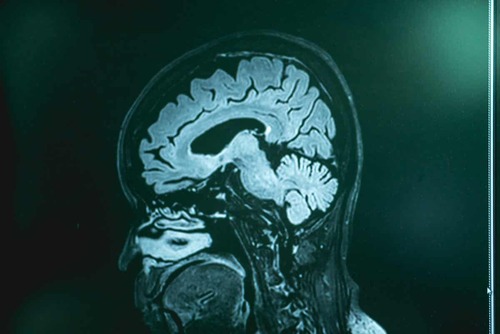

Gli esami di diagnostica per immagini (tomografia computerizzata e risonanza magnetica) invece non rilevano la malattia, ma possono escludere altre possibili patologie.